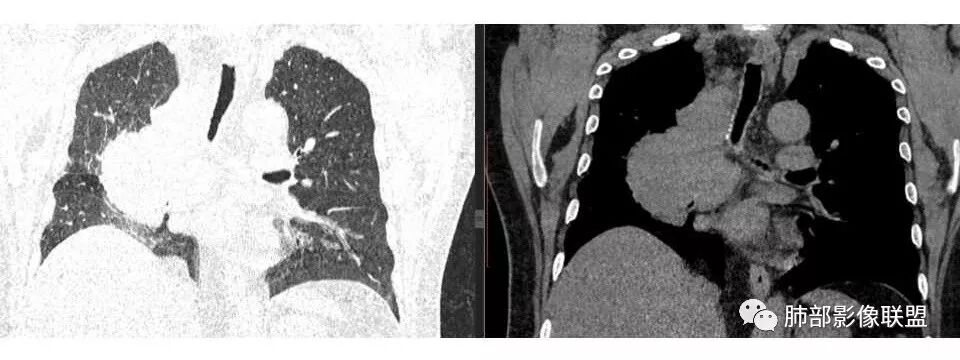

右侧胸膜增厚

我支持肺癌,每年体检没发现,提示进展迅速,没看到肺内大病灶,吸烟,支持小细胞癌可能

他的病理:多为小细胞癌,其次腺癌、鳞癌

这么大,肺门区,如果纵隔型肺癌,按理是中央型,常规——支气管为主

这一例表现反了,支气管稍受侵犯

宇宙星空: 嗯,淋巴结肿大为主

南边: 而且肺癌,一定受叶段的局限,这一例跨越右肺门,提示多个淋巴结融合

结果:小细胞肺癌

1.右肺上叶不规则结节影,右肺门及纵隔多结节并形成巨大块影,密度均匀,沿途支气管明显狭窄。

原发灶小或隐匿,肺门纵隔淋巴结异常增大,所谓“娘小崽大”常见于肺小细胞癌!

2.右肺小叶间隔增厚伴微小结节,提示癌性淋巴管炎。

3.注意患者年年体检未见明显异常!

一年之内,甚至几个月内出现的肺部肿块,也几乎将鳞癌、腺癌、类癌、肉瘤等肺原发肿瘤彻底排除在外!